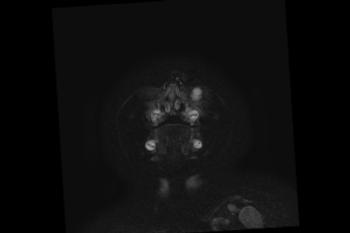

Figure 6. Images obtained in the case of a 24-year-old woman pregnant with twins, with characteristic rash at 9 weeks of pregnancy and confirmed Zika virus infection. (For each pair of images, the first image is of twin A, and the second image is of twin B.) At 14 weeks of gestational age, the fetal head size of both twins was normal. The head size never went below the 3rd percentile for either fetus in examinations at 19–28 weeks. (a, b) Sagittal and (c, d) axial fetal MR images were obtained at 36 weeks. (e, f) Axial and (g, h) surface reconstruction postnatal CT images and (i, j) axial T2-weighted and (k, l) coronal MR images were obtained 1 week after delivery at 38 weeks of gestational age. There is severe microcephaly with profound frontal lobe hypoplasia. Calcifications in the subcortical white matter at the gray matter–white matter junction are visualized. Both twins have a flattened appearance of the pons. The spinal cord is atrophic (best seen on a). Redundant skin is seen in the occipital region. There is polymicrogyria involving the frontal and parietal regions and atrophic cortex and white matter in the occipital regions. Each twin has hypoplasia of the corpus callosum, with prominent fornices. There is abnormal myelination in the occipital region that, in twin A (i), has the appearance of a cyst or septation within the ventricle. The cerebellum is somewhat small and nodular. There is lack of rotation of the hippocampi.